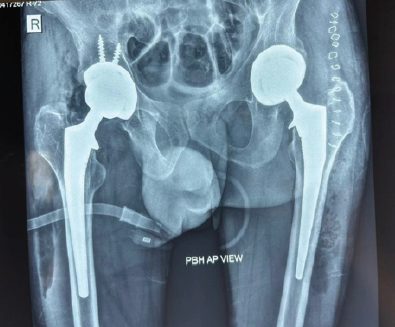

A 40-year-old male presented to our emergency department with an acute onset of pain in both his hips with inability to walk, after a fall from his bed, sustained at home the same day. On examination, the patient has bilateral hip joint tenderness and an inability to perform the straight leg test, with no distal neuromuscular deficit observed in both lower extremities. The patient did not have any other comorbidities. Plain radiographs revealed bilateral displaced intracapsular fractures of the femoral neck (Fig. 1).

Figure 1: Pre-operative anteroposterior pelvis X-ray showing bilateral displaced intracapsular fractures of the femoral neck.